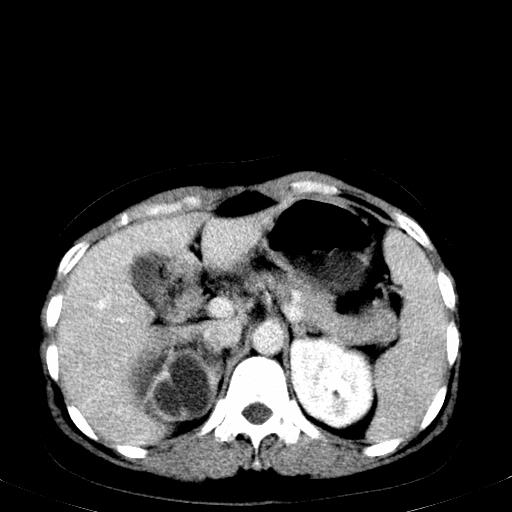

患者体检发现右肾体积增大,怀疑右肾积水

右肾重度积水,以肾盏积水明显,有分隔,上段输尿管轻度扩张,管壁增厚,考虑肾结核可能,请结合尿检查,胸部拍片排除肺结核。

右肾重度积水,建议ct向下扫描或逆行造影,左肾及左输尿管结石 .

患者尿常规正常,b超未发现明显结石,自身也无明显感觉异常。

请问多囊肾与肾积水怎么鉴别